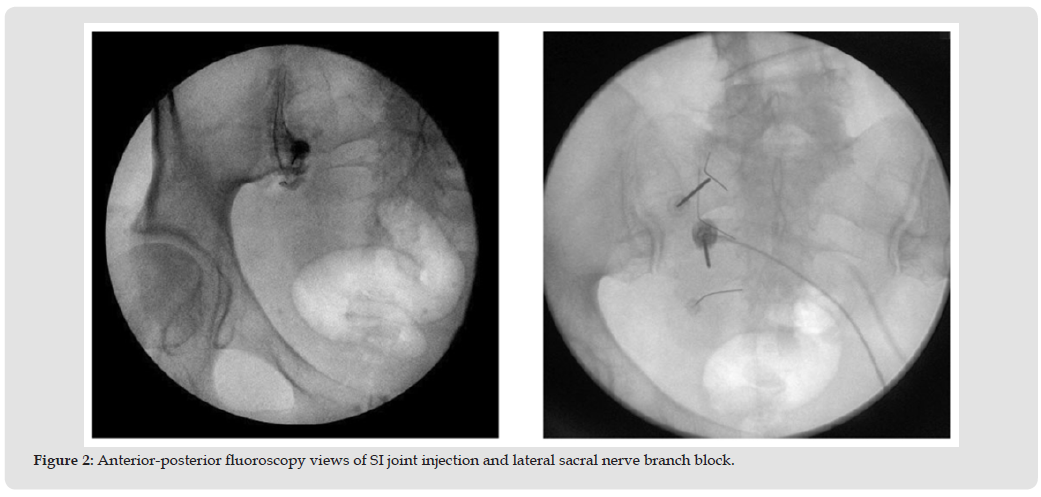

Although the liver and lungs are more common sites for overall metastasis, autopsy reports show that 60-70% of patients with metastatic cancer acquire spinal metastasis. The thoracic spine is the most common location for spinal metastasis (60-80%), followed by the lumbar spine (15-30%) and the cervical spine (<10%) [17]. Such involvement of the spine can cause instability and deformity and may lead to complications such as pathologic vertebral compression fractures (pVCF) and metastatic epidural spinal cord compression (MESCC). Approximately one in ten patients with spinal metastases will develop MESCC, and another 12.6% will develop a pVCF [18]. The SI joint can be subjected to indirect stress from primary, secondary, or metastatic cancer in the spine, resulting in pelvic imbalances and unequal weight distribution. By the time bone metastasis occurs, treatment aims to control pain and maintain quality of life. Understanding the epidemiology should increase awareness of the first symptoms and promote early diagnosis, emphasizing the prevention of future skeletal complications, and thus improving overall outcomes [17] (Figure 2).